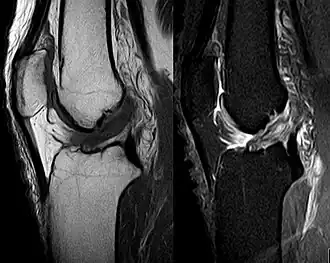

Anterior cruciate ligament tear seen on MRI. T1 left, right PDW.

Though clinical examination in experienced hands can be accurate, the diagnosis is usually confirmed by magnetic resonance imaging, which provides images of the soft tissues like ligaments and cartilage around the knee.[1] It may also permit visualization of other structures which may have been coincidentally involved, such as the menisci or collateral ligaments.[36] An x-ray may be performed in addition to evaluate whether one of the bones in the knee joint was broken during the injury.[9]

MRI is perhaps the most used technique for diagnosing the state of the ACL, but it is not always the most reliable technique as the ACL can seem healed on chronic cases with the proliferation of synovial scar tissue when treated conservatively.[37]

MRI is particularly useful in cases of partial tear of the ACL. The anteromedial band is most commonly injured compared to the posterolateral band.[38]